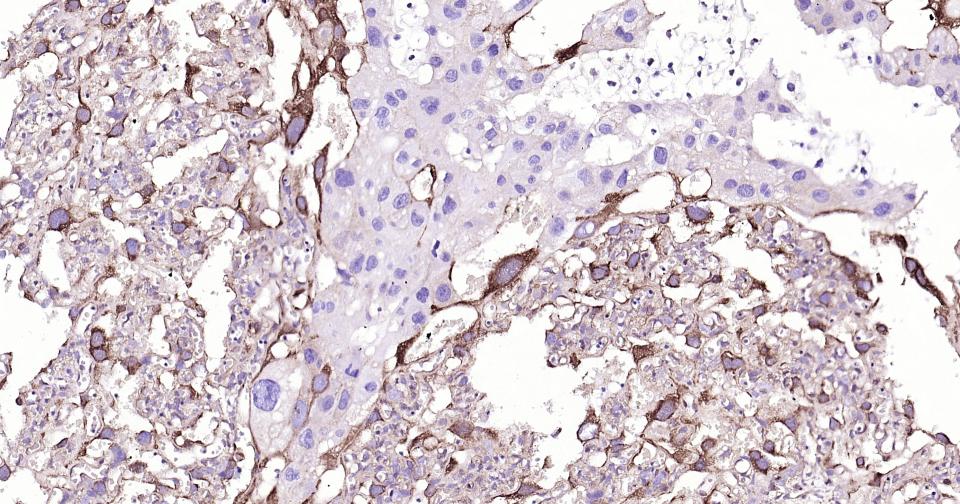

Paraformaldehyde-fixed, paraffin embedded Human Colon Cancer; Antigen retrieval by boiling in sodium citrate buffer (pH6.0) for 15 min; Antibody incubation with MSI2 Monoclonal Antibody, Unconjugated(bsm-61244R) at 1:200 overnight at 4°C, followed by conjugation to the bs-0295G-HRP and DAB (C-0010) staining.